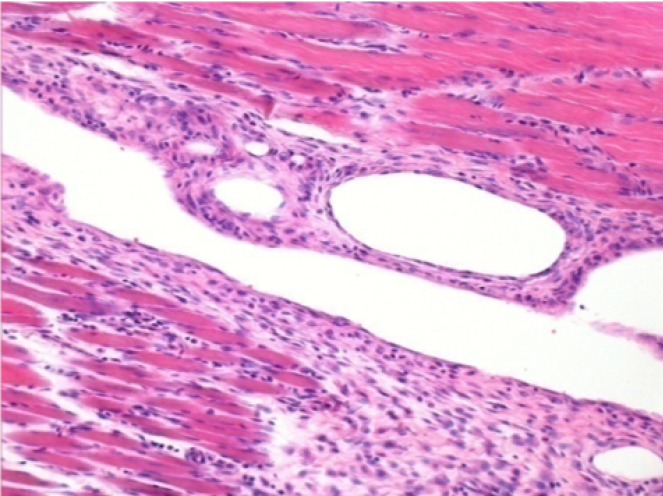

Endopeel Enjeksiyonundan 10 gün sonra sağ pretibial kasta 0.1ml.

Burada lenfositlerle çevrili vakuollerin oluşumunu görebilirsiniz. Vakuoller doku nekrozundan farklıdır. Lenfositlerin varlığı, hücre zarlarının geçirgenliği ile ilgilidir.